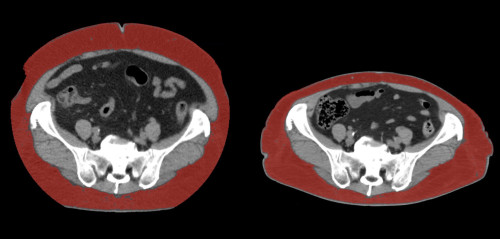

②

40代・女性(ご本人のご厚意で画像提供)

治療内容:チルゼパチド2.5mgの週1回自己注射による脂肪減少と脂肪肝改善

治療期間: 6ヶ月(26週)((用量は2.5mgから開始し最大で15mg。減量効果が得られる必要用量には個人差があります。))

費用:自由診療の場合は4400円(税込)×26(週)=114400円

想定されるリスク・副作用:下記に副作用を記載

※医療広告ガイドラインに準拠して表記

1:脂肪の減少

皮下脂肪の減少(赤色部分)